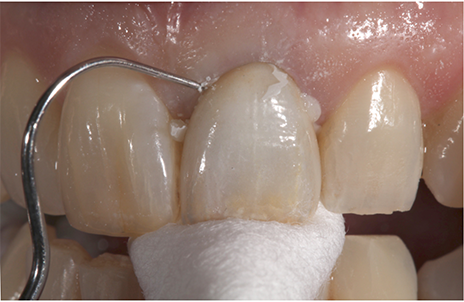

A 60-year-old female presented upon referral from her general dentist for prosthodontic treatment when she requested a new full-coverage crown restoration for tooth #9. She fractured the tooth participating in gymnastics as a child. The tooth was initially restored with composite resin, but when it became discolored, endodontic therapy followed by placement of a cast post, core and crown was performed. The ceramic on the mesial-incisal portion of the crown had fractured (Fig. 1), so the patient reported that it was finally time to replace it.

Fig. 1 Fig. 2

The patient also reported that she was never happy with the restoration, and she also was unhappy with the incisal chipping on tooth #8. Since she was about to embark on a new career, she wanted a smile she felt confident about.